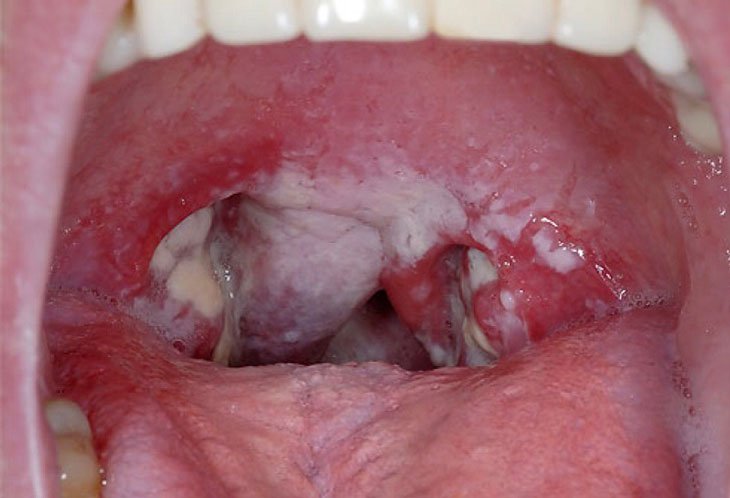

Bệnh bạch hầu: nguyên nhân, triệu chứng, chẩn đoán, điều trị